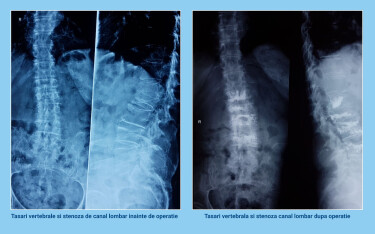

Operatie hibrid pentru tasare vertebrala multipla si stenoza severa de canal lombar

Cu putin timp in urma, pacienta noastra, doamna M., in varsta de 73 de ani, a fost operata dupa ce a primit diagnosticul de osteoporoza vertebrala severa si tasari vertebrale multiple (4 vertebre). Pacienta suferea de multiple boli asociate, precum hipertensiune arteriala, emaciere si anemie pronuntata. Mai mult decat atat, doamna M. era imobilizata la pat de cateva saptamani din cauza durerilor din regiunea lombara si a piciorului drept.

Aceasta interventie de tip hibrid, efectuata in premiera la spitalul SANADOR, a constat in reducerea presiunii stenozei de canal lombar, microchirurgical, cu ajutorul unui microscop operator si, ulterior, injectarea de ciment in corpii vertebrali tasati. Manevra a fost facuta cu ajutorul unor ace mai groase, denumite ace trocare, introduse prin piele.

Operatia, care a durat patru ore, a fost un adevarat succes, pacienta noastra reusind sa se ridice din pat la doar 2 zile dupa operatie! Dupa numai patru zile, pacienta a plecat acasa, pe picioarele ei si a revenit ulterior pentru scoaterea firelor. De asemenea, doamna M. a a renuntat la tratamentul antiinflamator si pentru durere pe care il facea, pentru ca durerile care o chinuisera cateva luni bune au disparut in totalitate!